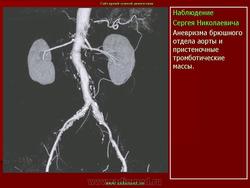

Аневризмы брюшной аорты